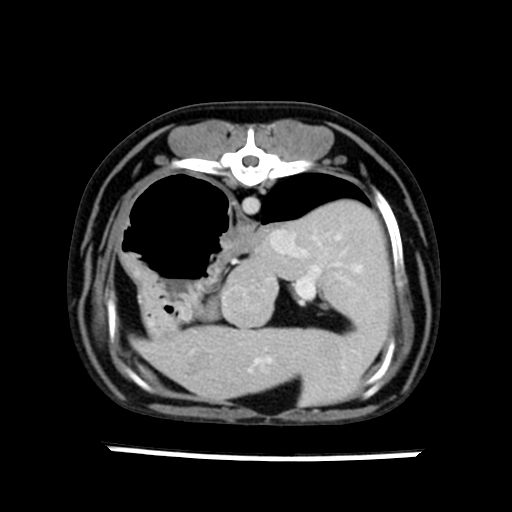

prescritto esame TAC

sequenza immagini limitata al fegato reni e surreni

le immagini ecografiche rispetto alla tac datano circa 7 mesi prima ,le surrenali sono normali nonostante il test acth sia risultato positivo .all’esame TAC dopo diversi mesi risultano aumentate armonicamente nel volume e si individua un forte sospetto di adenoma ipofisario .

sospetto adenoma ipofisario vs. meno probabilmente meningioma della base; intertiziopatia polmonare; lesione espansiva epatica, verosimilmente del lobo laterale sinistro, di sospetta natura neoplastica; lesioni spleniche di natura da definire; iperplasia/ipertrofia delle ghiandole surrenali, bilateralmente; vertebra di transizione del rachide toracico; tenosinovite cronica del muscolo bicipite brachiale di destra.

la tac dopo 7 mesi permette misure tridimensionali 5,2 x 9,2 x 4,5 cm (forma piu’ allungata )